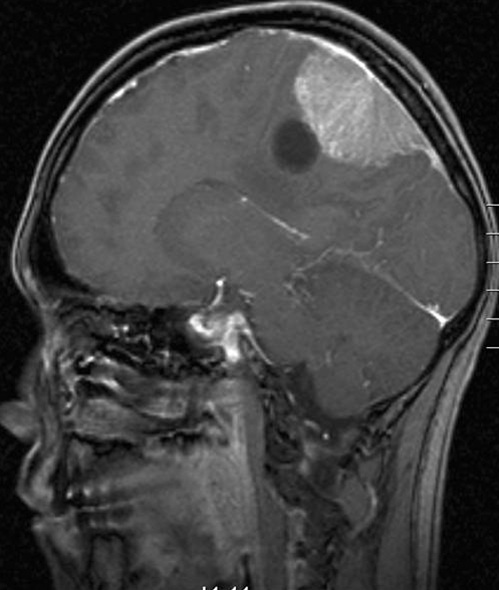

Hjerne, Meningeom med cyste, MR

MR-skanning af hovedet med kontraststof viser et bredbaseret meningeom med kraftig kontraststof-opladning. Der er yderligere en cyste ved siden af meningeomet.

Gengivet med tilladelse fra Radiologisk afdeling, Universitetssygehuset Nord-Norge